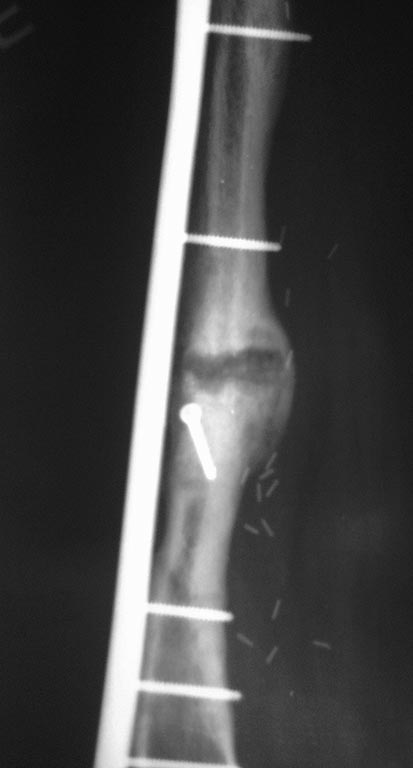

[Ortho] Саркома бедра

добавлю снимок